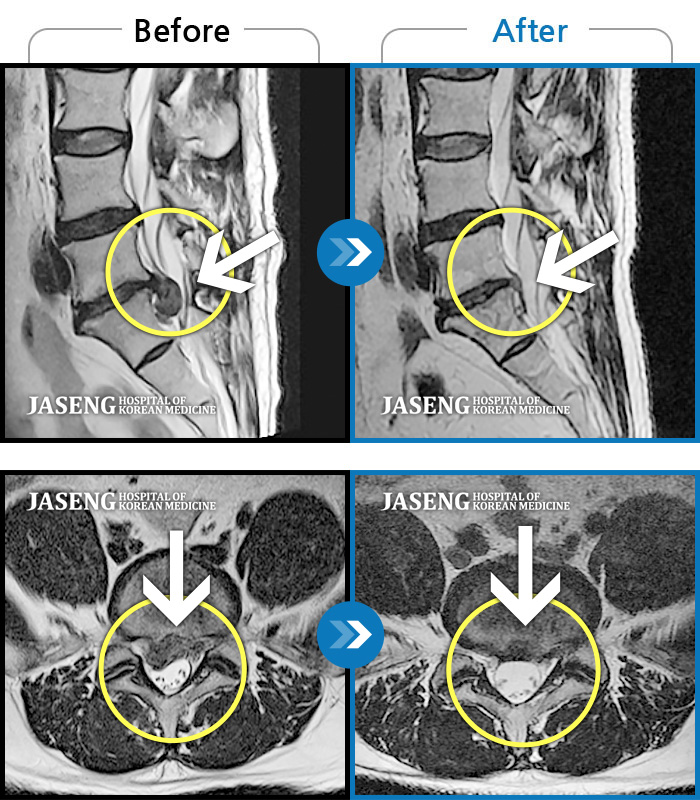

허리디스크

일산 · 김태용 원장

허리와 좌측 하지 방사통이 심하시어 보행이 거의 힘들었다.

촬영시기

2021.03.06 ~ 2021.07.15

2021.07.23